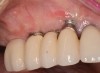

(15.) Due to physiologic remodeling of the alveolar ridge, facially inclined implant positions, and ineffective augmentation at time of placement, these three implants are experiencing mucosal recession.

Figure 15

(16.) Following flap reflection, the buccal bone deficiencies are evident.

Figure 16